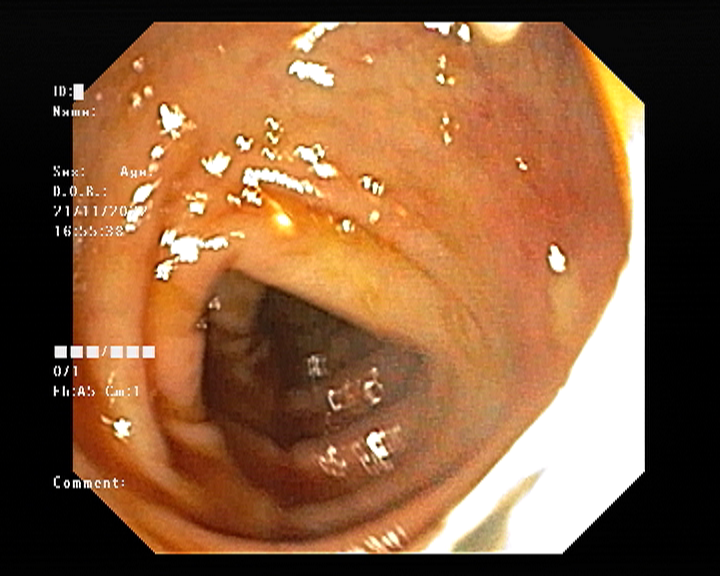

ERCP (Endoscopic Retrograde Cholangiopancreatography) is a specialized procedure used to diagnose and treat conditions affecting the bile ducts, gallbladder, and pancreas. Problems such as bile duct stones, blockages, strictures, and recurrent jaundice often require ERCP for accurate diagnosis and effective relief.

At Sapphire Gastroenterology Center, ERCP is performed with advanced technology to safely remove stones, relieve obstructions, and place stents when needed. This helps reduce pain, prevent infections, and avoid major surgery in many cases. Early ERCP intervention can prevent serious complications such as cholangitis, pancreatitis, and long-term liver damage.